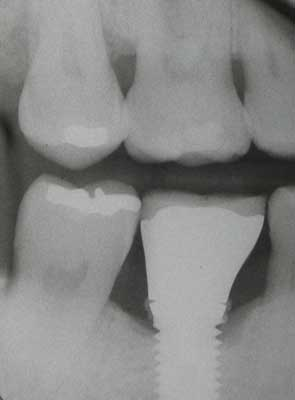

Fig. 6: Radiograph reveals retained cement.